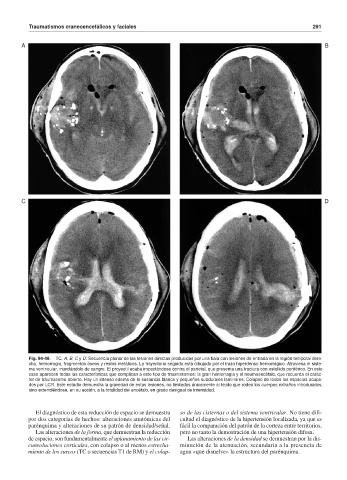

Fig. 94-49. TC. A, B, C y D: Secuencia planar de las lesiones directas producidas por una bala con lesiones de entrada en la región temporal dere-

cha, hemorragia, fragmentos óseos y restos metálicos. La trayectoria seguida está dibujada por el trazo hiperdenso hemorrágico. Atraviesa el siste-

ma ventricular, inundándolo de sangre. El proyectil acaba impactándose contra el parietal, que presenta una fractura con estallido periférico. En este

caso aparecen todas las características que complican a este tipo de traumatismos: la gran hemorragia y el neumoencéfalo, que recuerda el carác-

ter de traumatismo abierto. Hay un intenso edema de la sustancia blanca y pequeños subdurales laminares. Colapso de todos los espacios ocupa-

dos por LCR. Este estudio demuestra la gravedad de estas lesiones, no limitadas únicamente al tejido que rodea los cuerpos extraños introducidos,

sino extendiéndose, en su acción, a la totalidad del encéfalo, en grado desigual de intensidad.